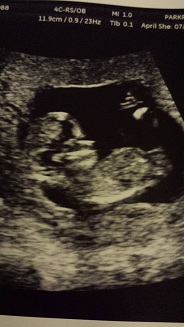

Attachment 20068Hi! This will be my first baby and I am SO excited to find out what we're having! It's so much fun doing these gender predictions and we'll be happy with either gender, but I'm trying to figure out what everyone is calling the "nub theory"...I'm not sure what I'm looking for, so any help is appreciated!!